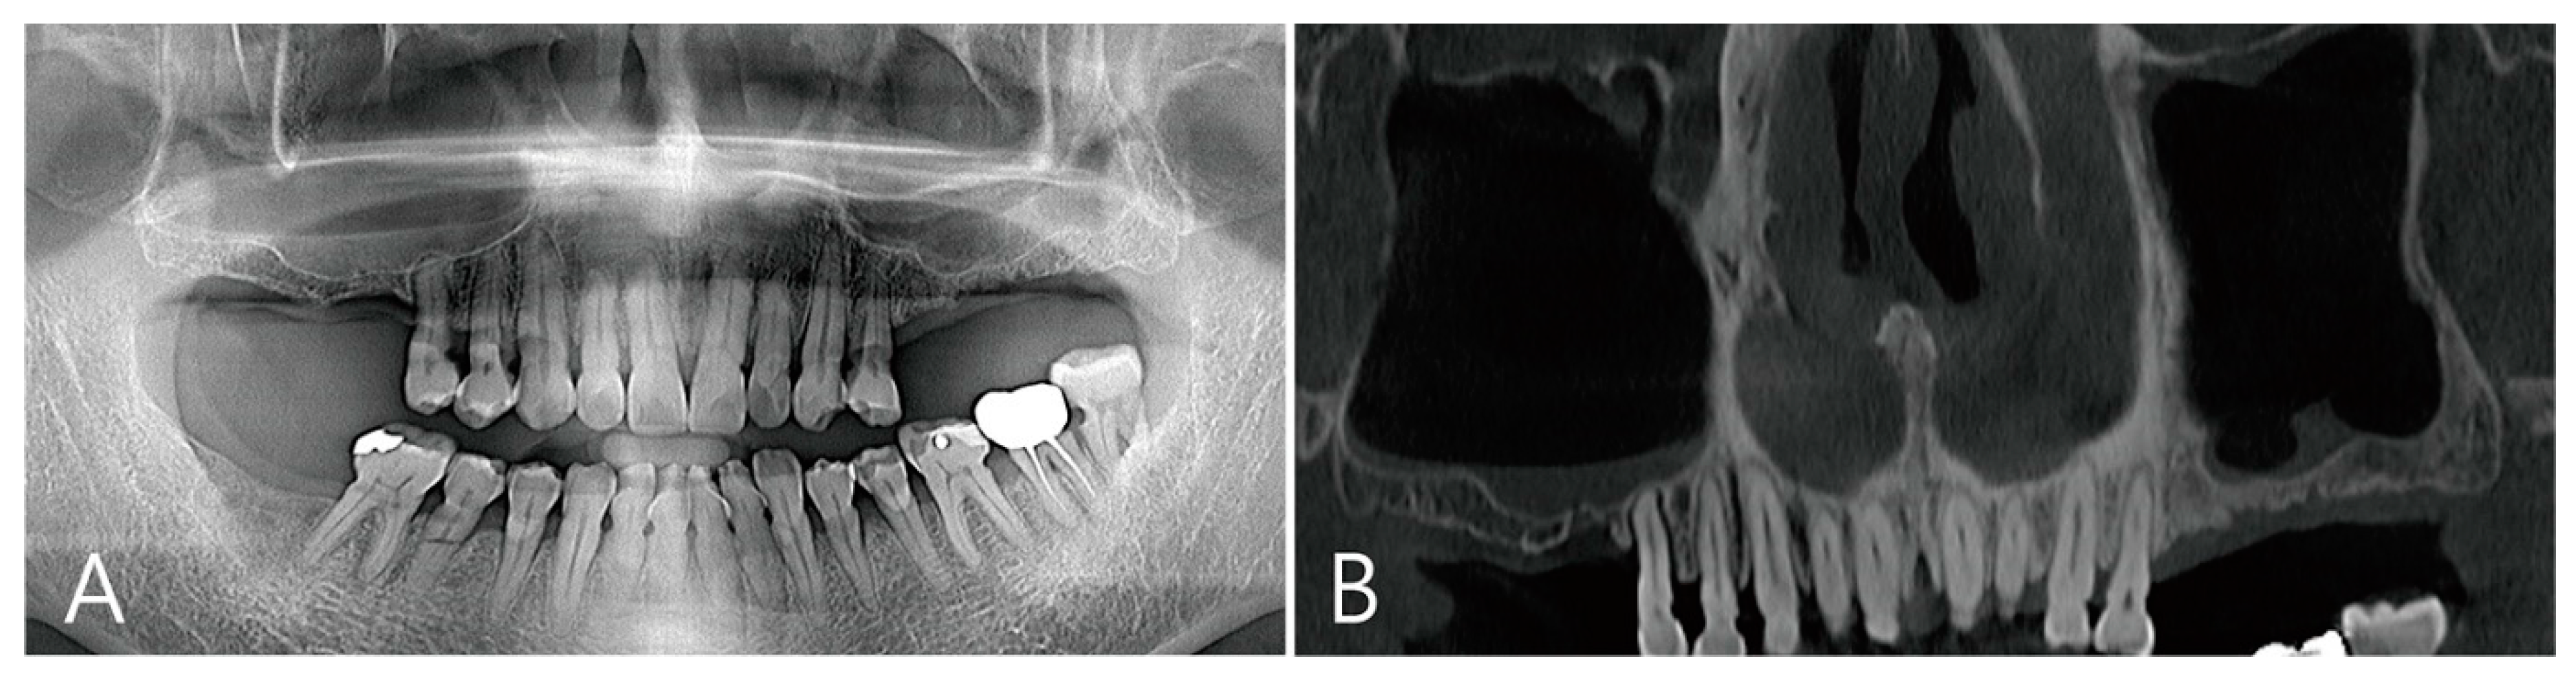

2.5. Case 4

A 75-year-old female who was a non-smoker visited a private clinic to have the implant placed in the edentulous ridge of the maxillary left posterior region (Table 1). This patient was taking antihypertensive and antihyperlipidemic drugs. Preoperative panoramic radiography and CBCT scan were performed. The left maxillary sinus was severely pneumatized and had a minimal residual bone height of 2–4 mm, rendering normal implantation impossible (Figure 10A,B). In the maxillary sinus, membrane thickening was confined to the sinus floor and no sinus pathology was observed in the remaining areas (Figure 10B). Lateral MSA and simultaneous implant placement were planned on the left maxillary sinus.

Figure 10. Case 4. Preoperative panoramic radiography and CBCT scan were performed: (A) the left maxillary sinus was severely pneumatized and had minimal residual bone height; (B) in the maxillary sinus, membrane thickening was confined to the sinus floor and no sinus pathology was observed in the remaining areas.